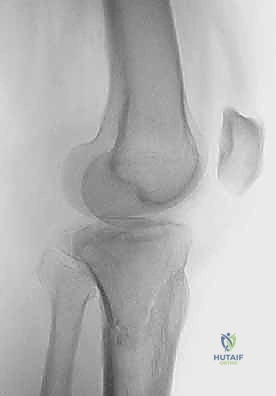

2. التصوير الإشعاعي (X-rays)

الخطوة الأولى هي التقاط صور أشعة سينية من عدة زوايا (أمامية خلفية، وجانبية). تعطي الأشعة السينية فكرة عامة عن وجود الكسر وموقعه، لكنها غير كافية لتقييم الكسور ثنائية اللقمة المعقدة.

3. الأشعة المقطعية المحوسبة (CT Scan) - المعيار الذهبي

لا يمكن إجراء جراحة لكسر ثنائي اللقمة دون إجراء أشعة مقطعية (يفضل مع إعادة بناء ثلاثية الأبعاد 3D).

* توفر الأشعة المقطعية خريطة دقيقة لكل شظية عظمية.

* تحدد مقدار الانخساف في السطح المفصلي بالمليمتر.

* تكشف الشظايا المخفية، خاصة في الجزء الخلفي من الركبة (Posterior Coronally oriented fragments) والتي تتطلب خطة جراحية خاصة لتثبيتها.